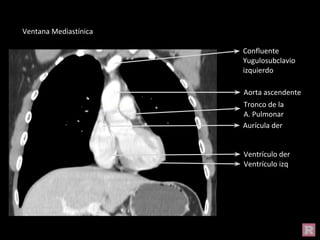

Aorta ascendente

Aurícula der

Tronco de la

A. Pulmonar

Ventrículo izq

Ventrículo der

Confluente

Yugulosubclavio

izquierdo

Ventana Mediastínica